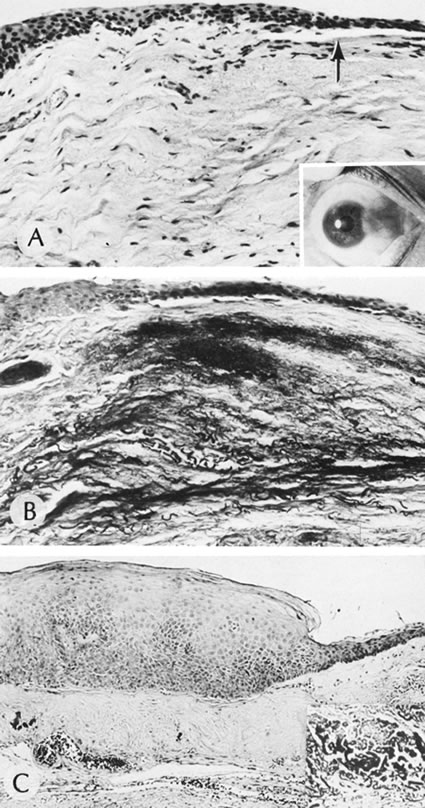

NONSPECIFIC OPACITIES

There are multiple nonspecific types of congenital corneal opacities. Although arrested embryogenesis or intrauterine inflammation may cause the entity, the opacities have the same clinical characteristics as acquired changes following trauma. In order of progressive severity, the degree of opacification is called a facet when only Bowman's membrane is involved; a nebula when the area of opacification is diffuse, cloudlike, and has indistinct borders; a macula when the area is dense and has a circumscribed border; and a leukoma when the cornea is opaque. Adherent leukoma is a subgroup in which a portion of iris is fused to the posterior surface of the opaque corneal tissue, similar to the findings of some healed acquired corneal perforations (Fig. 2).

Fig. 2. Adherent leukoma. A. Proliferated fibrous tissue attaches the iris to the cornea through a gap in Descemet's membrane of a 3-week-old wound. An overlying scar(s) is present through the full thickness of the cornea. After organization and shrinkage of the fibrous membrane, the scar will look much like the scar of adherent leukoma seen in B. Peripheral adherent leukoma (arrow) in a 12-year-old girl who had accidental perforation of the globe by a pair of scissors 5 weeks previously. The perforation of the cornea was repaired on the day of the injury. Sympathetic uveitis developed 2 days before the photograph was taken. C. The peripheral iris is adherent to the corneal stroma through a gap in Descemet's membrane. The overlying stroma is scarred. (Courtesy of SEI Photoarchives.)